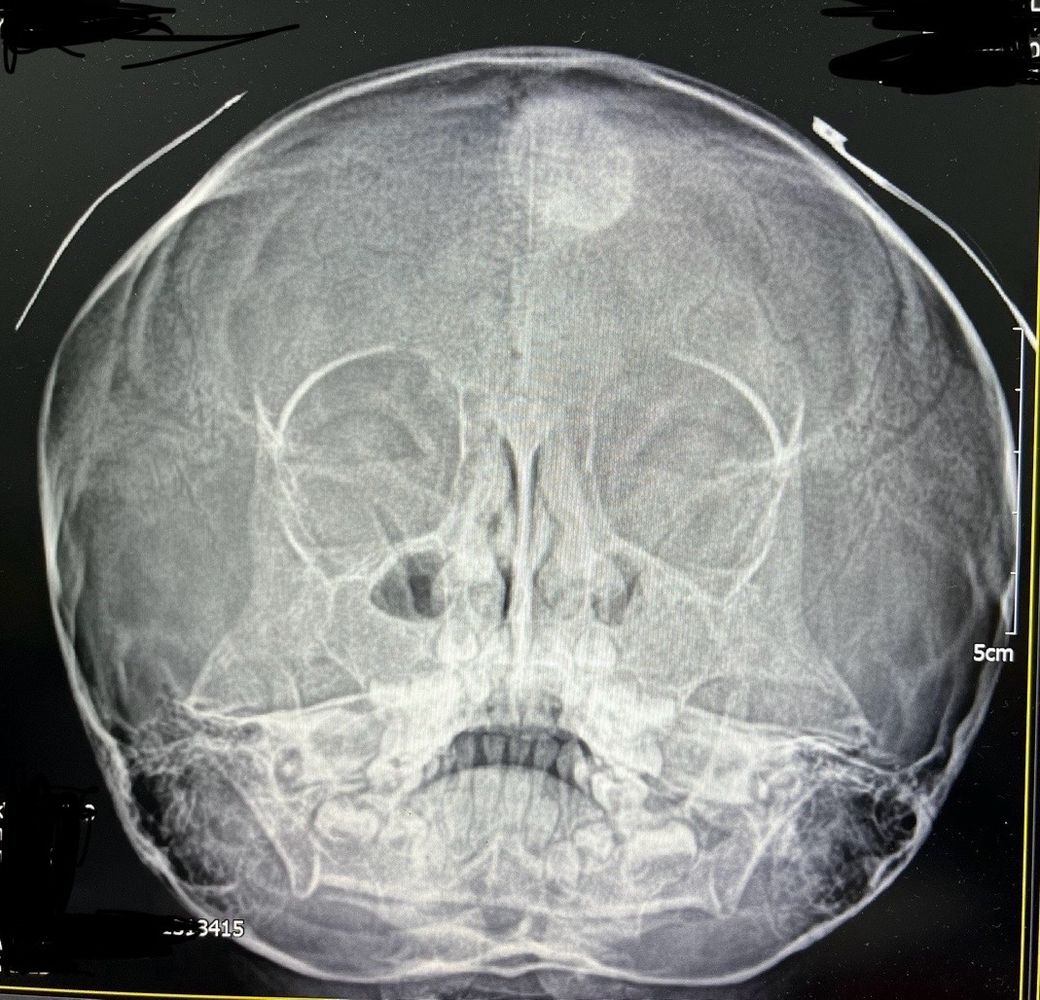

5세 여아입니다 얼마전 부비동 엑스레이사진 입니다

머리에 흰색 원이 보이는데요

소아과 원장님도 처음 보는거라시네요

무엇일까요?

부비동 엑스레이에서 머리에 흰색 원이 보인다는 것은 확실히 걱정스러운 일일 수 있습니다. 일반적으로 엑스레이에서 흰색 원이 보이는 것은 기타 이상이나 특이한 문제를 의심해 볼 수 있습니다.

의심해 볼 수 있는 문제로는 부비동에 농이 차서 엑스레이에서 흰색으로 나타날 수 있습니다. 하지만 보통 이 경우에는 다른 증상도 동반됩니다.

혹은 엑스레이에서는 종양, 결절, 또는 다른 비정상적인 조직이 나타날 수도 있고, 부비동 외에도 두개골에서의 변형이나 이상이 엑스레이에 나타날 수 있습니다.

• 엑스레이 사진만 놓고 구체적으로 무엇인지 판단 내리기는 어렵습니다. 원형의 이물질 같은 것이 보이는데 촬영 상 우연히 기계의 이상이 발생하거나 한 것이 아니라면 일단 분명 이상 소견이라고 판단을 하여야 하겠습니다. 관련하여서는 CT 등의 보다 정밀한 검사를 통하여 더 자세하게 어떠한 것인지 파악해보는 것이 필요할 것으로 사료됩니다. 현재로서는 신경외과로 가셔서 정밀하게 파악해보는 것을 권고드립니다.